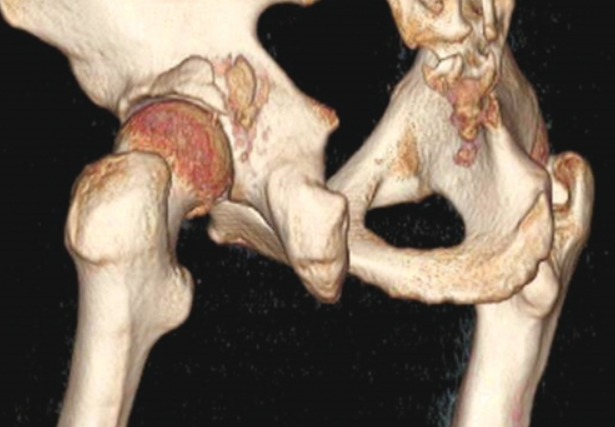

患者1周前于车祸中受伤,受伤时患者位于副驾驶座位,所坐车辆与前车追尾。车辆发生撞击后,患者出现左髋部畸形、剧烈疼痛及活动障碍。外院影像学检查诊断为左髋关节脱位、左髋臼骨折、左股骨头骨折(图4~图6)。

图5 闭合复位左髋关节后,CT三维重建示左髋臼后壁骨折